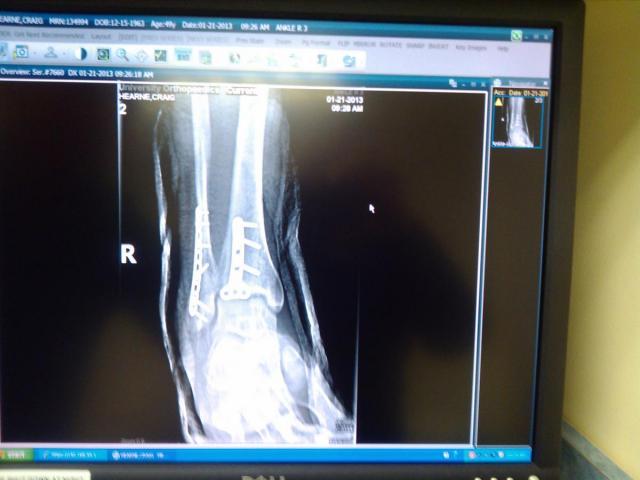

varosd 1,185 #90 Posted January 23, 2013 Craig, Taking cast off and getting into PT is the big benefit of having ORIF(Open reduction,internal fixation). if they just casted a fracture, you have to wait 4-6 weeks in cast then remove and then PT. by putting in plates and screws (better than grade 8) you can start PT and get range of motion and strength back sooner. of course PT will be painful! PT person: Mr AMC Rules, you are gonna hate me, but I'll have you walking soon" :rolleyes: 2 Share this post Link to post Share on other sites

varosd 1,185 #94 Posted January 24, 2013 Craig, looks like you have another problem looks like plantar wart on foot photo? 1 Share this post Link to post Share on other sites

AMC RULES 37,256 #96 Posted January 25, 2013 Craig, looks like you have another problem looks like plantar wart on foot photo? Good eye Don, been there most of my adult life...has never been a problem though. Share this post Link to post Share on other sites